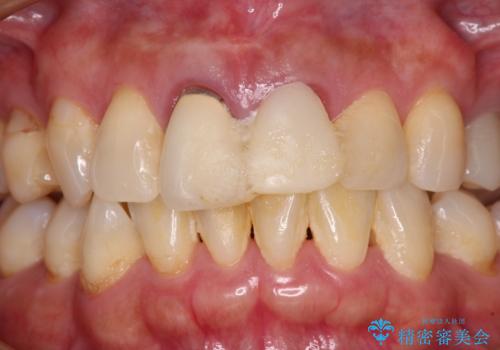

- 治療中の前歯の仮歯がひどい状態であるとのことで来院された患者様です。

治療中の前歯は根管治療の途中であり、根尖部に痛みを感じる状態でした。

根管治療後に痛みは軽減しましたが、僅かな痛みが続くとのことで、レントゲン写真では病変は認められなかったものの、歯根端切除を行うこととしました。処置後は痛みは全くなくなり、安心して補綴治療を行うことができました。